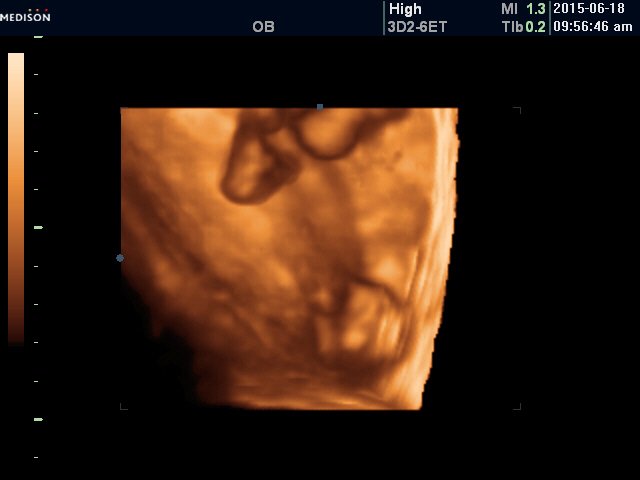

我今天做了四维检查,怀孕6个月 医生给我拍了张照片,我想知道这是啥,哪个部位? 点击展开 匿名用户 2015-06-19 19:51 满意回答 你好,这是看不清楚的,怀孕六个月做完四维彩超截耗检查后 ,是需要看检查结果的,只要没有胎儿畸形,是没事的,其丰剪化次建议你检查后听医生的,怀孕中期行四维次坊彩超检查主要排出胎儿先天性畸形的。 shenglongxiao 2015-06-19 20:13 宝宝知道提示您:回答为网友贡献,仅供参考。 相关问题 今天去照的四维 第一张小鬼的照片哦 今天第二次胎检医生说我家大宝贝58天了 好高兴啊 第一张是7月5日我还不知道怀孕呢,去医院验血结 今天本来想去看看到底是不是四维彩超,医生居然不说,给我采白带叫我检查一下,说我白带黄,然后开了一张